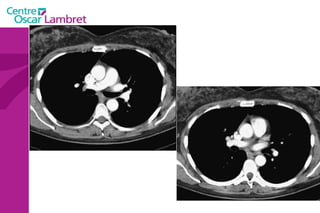

Le coeur  comprend quatre cavités :  deux cavités droites, formées par l’oreillette (ou atrium) et le ventricule droit.  deux cavités gauches, formées par l’oreillette (ou atrium) et le ventricule gauche.  Les cavités droite et gauche sont totalement séparées par une cloison (septum).  Ces cavités sont connectées à des veines et des artères qui conduisent le sang venant ou partant du coeur.  L’appareil circulatoire

Les 2  atriums  ont un petit diverticule : les auricules Le cœur repose sur le diaphragme et est situé au niveau de la partie antérieure et inférieure du médiastin. Le coeur est bordé latéralement par les poumons qui le recouvre partiellement. Les 4 cavités du coeur sont limitées par des sillons. Le  sillon coronaire le sillon inter atrial  Le sillon inter ventriculaire ou septum L’appareil circulatoire

L’appareil circulatoire L’ aorte  est la plus grande artère du corps.  Elle part du ventricule gauche du coeur et apporte notamment du sang oxygéné à toutes les parties du corps via la circulation. Elle est divisée en aorte thoracique et aorte abdominale. L’aorte thoracique  comprend trois segments : l'aorte ascendante, horizontale et descendante.